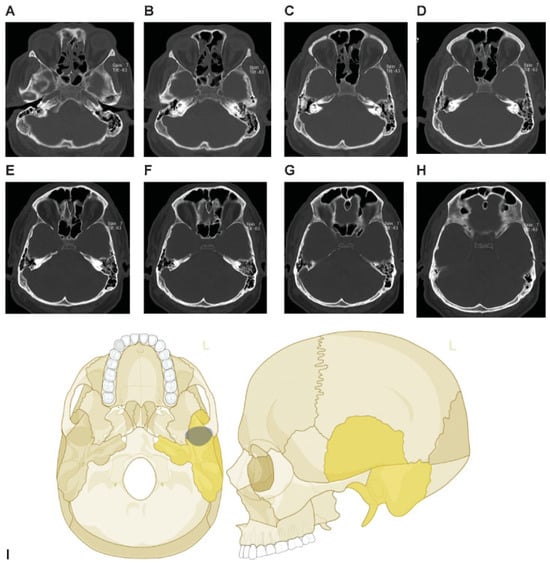

Fractures of the walls of the paranasal sinuses with the presence or the absence of opacification of the paranasal sinuses on CT imaging (i.e., blood or other fluids) are also documented. Illustrative examples are presented in Figure 3 and Figure 4A.

Figure 3. Examples of fractures and definitions. (A) Depressed fracture (displaced toward the brain) of the parietal bone. (B) Multiple fractures, depressed on the right frontal bone, displaced on the left frontal bone, with involvement and opacification of the frontal sinus bilaterally. (C) Transverse fracture line through the right petrous bone, another fracture line through the right apex petrosis, opacification of the left mastoid with fracture at the rostral rim. (D) Transverse maximum intensity projection (MIP) – reconstruction of the skull base with fragmented fracture of the right middle skull base fossa. (E): Nonfragmented fracture of the left parietal bone. (F) Curved MIP—reconstruction of the occipital bones with fragmented fracture, displaced but not depressed.